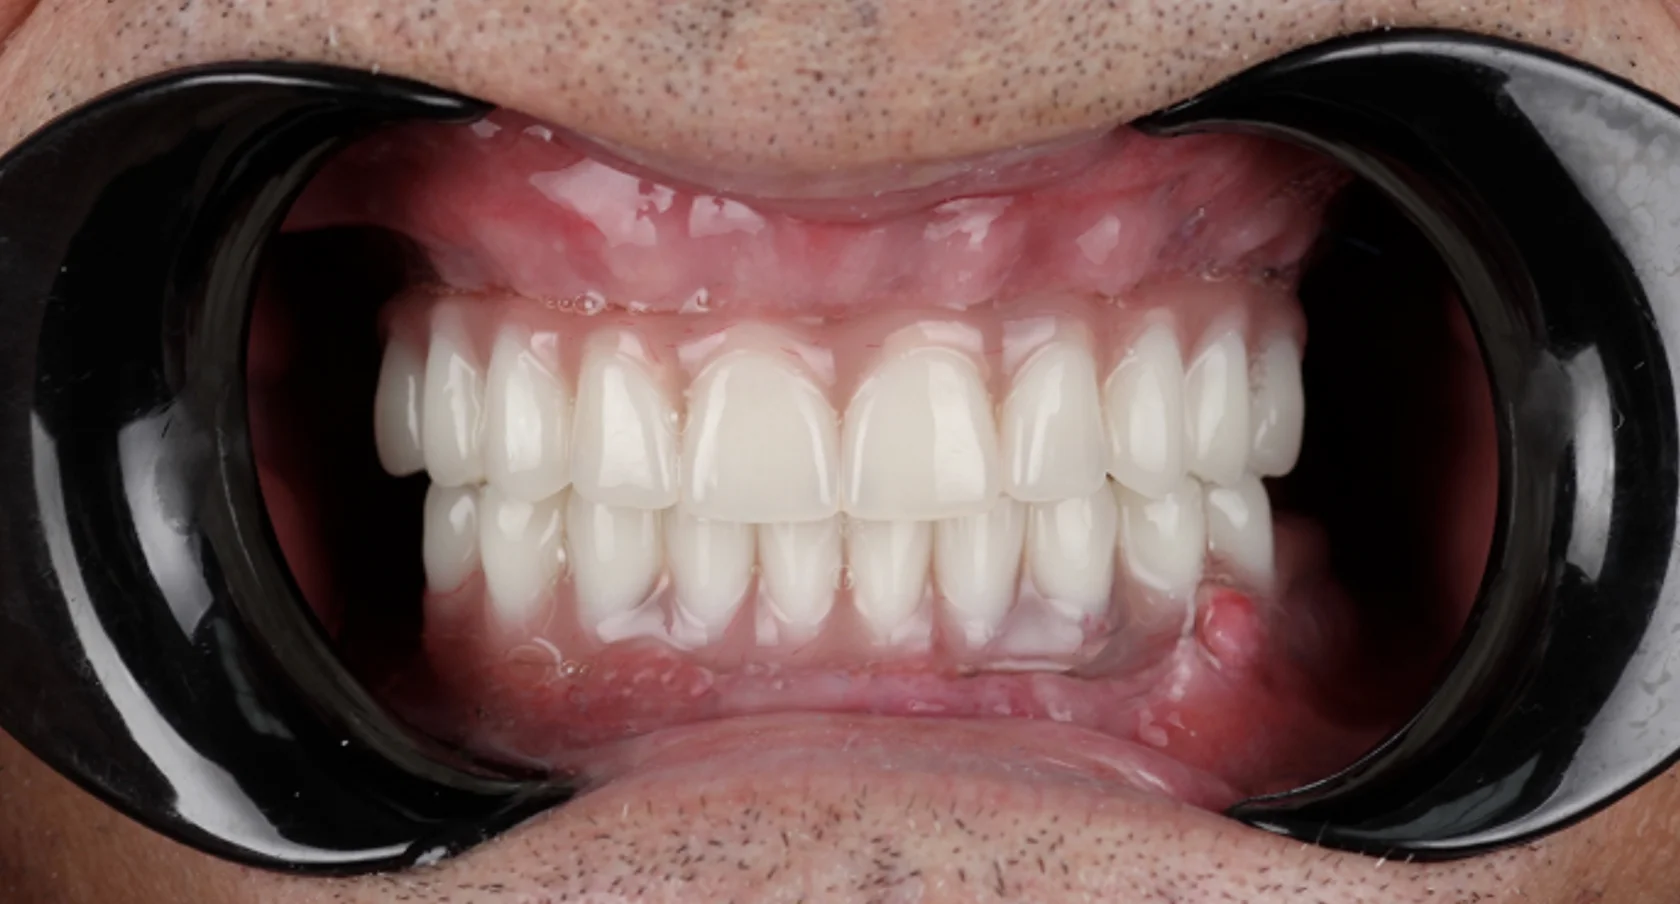

Долгое время пациентка стеснялась улыбаться и избегала фотографий из-за проблем с зубами и неудобных съёмных конструкций. Она откладывала лечение, считая, что восстановление будет долгим и тяжёлым. Отсутствие зубов на верхней и нижней челюсти требовало надёжного и долгосрочного решения.

На консультации мы подробно обсудили все варианты и выбрали современное и комфортное решение. Было выполнено полное восстановление зубных рядов по концепции All-on-6 с немедленной нагрузкой. В день операции установлены имплантаты и несъёмные протезы.

Сегодня пациентка улыбается уверенно, свободно общается и возвращается к привычной активной жизни без прежних ограничений.